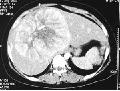

临床病例讨论:肝内巨大占位性病变